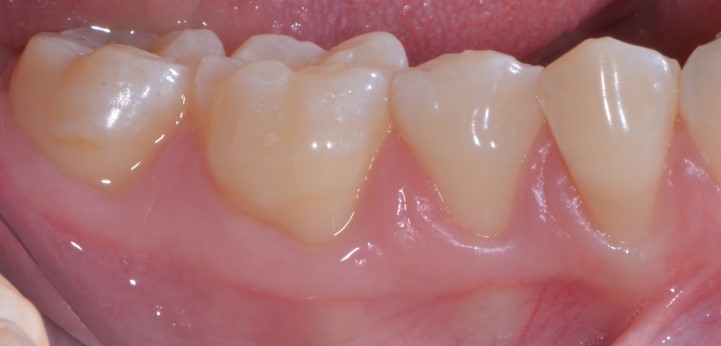

Perché, secondo te, Francesca ha accettato di farsi tagliuzzare in 2 punti per risolvere questo problema? Te lo spiego io: perché io sapevo di poterle dare questa guarigione a 10 giorni

gestione dei tessuti molli - aspetto dei tessuti molli 04

e questa a sei mesi.

gestione dei tessuti molli - aspetto dei tessuti dopo guarigione

Questa consapevolezza mi ha permesso di proporle la cosa nel modo giusto e lei non ha avuto dubbi nell’accettarla. E anche se qualcuno nel mondo parodontale critica la chirurgia mucogengivale, sono convinto che abbia fatto benissimo ad accettarla!